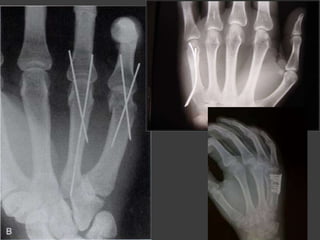

Tratamiento quirurgico

(indicación)

 Falla del tto conservador

 Fracturas expuestas

 Fracturas de 2 o más MTC

 Fx articular desplazada

 Fx con rotación

 Fx con acortamiento > a 3mm

 Fx angulada>10-20°

Metodos de reducción

Transversales

Oblicua

Conminuta